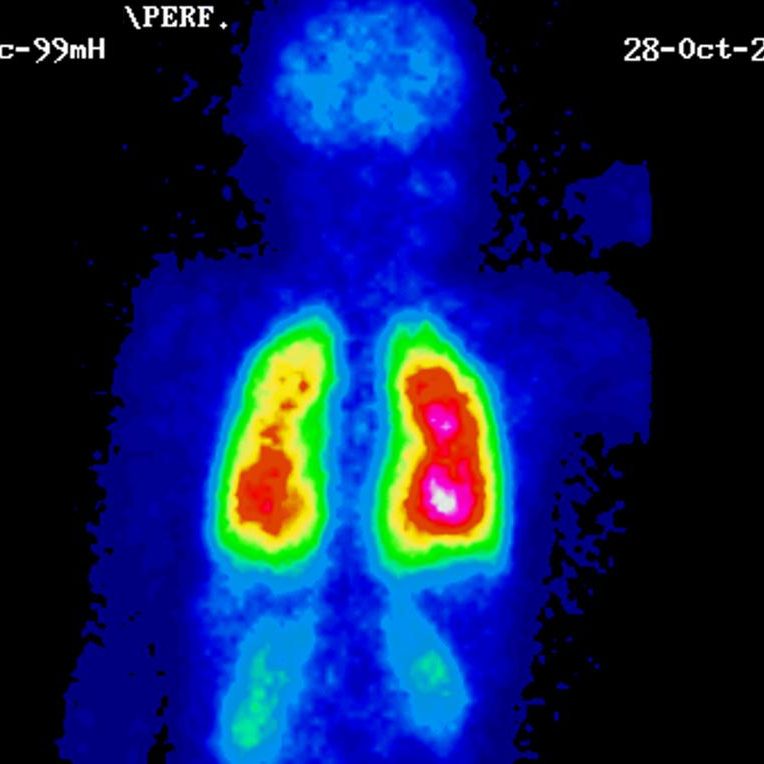

Una gammagrafía ósea implica inyectar una cantidad muy pequeña de material radiactivo (marcador) dentro de una vena. La sustancia viaja a través de la sangre hasta los huesos y órganos. A medida que esta va desapareciendo, emite un poco de radiación. Esta es detectada por una cámara que lentamente escanea el cuerpo.

Toma imágenes del marcador que hay en sus huesos. El técnico puede solicitarle que cambie de posición durante el procedimiento. Esto ayuda a obtener imágenes desde diferentes ángulos. Una gammagrafía ósea de todo el cuerpo tarda aproximadamente 1 hora en completarse.

La cámara gamma detecta las emisiones de energía de la radiosonda en su cuerpo y las convierte en una imágen. La cámara gamma de por sí no emite ninguna radiación. Tiene detectores de radiación denominados cabezas de cámara gamma.